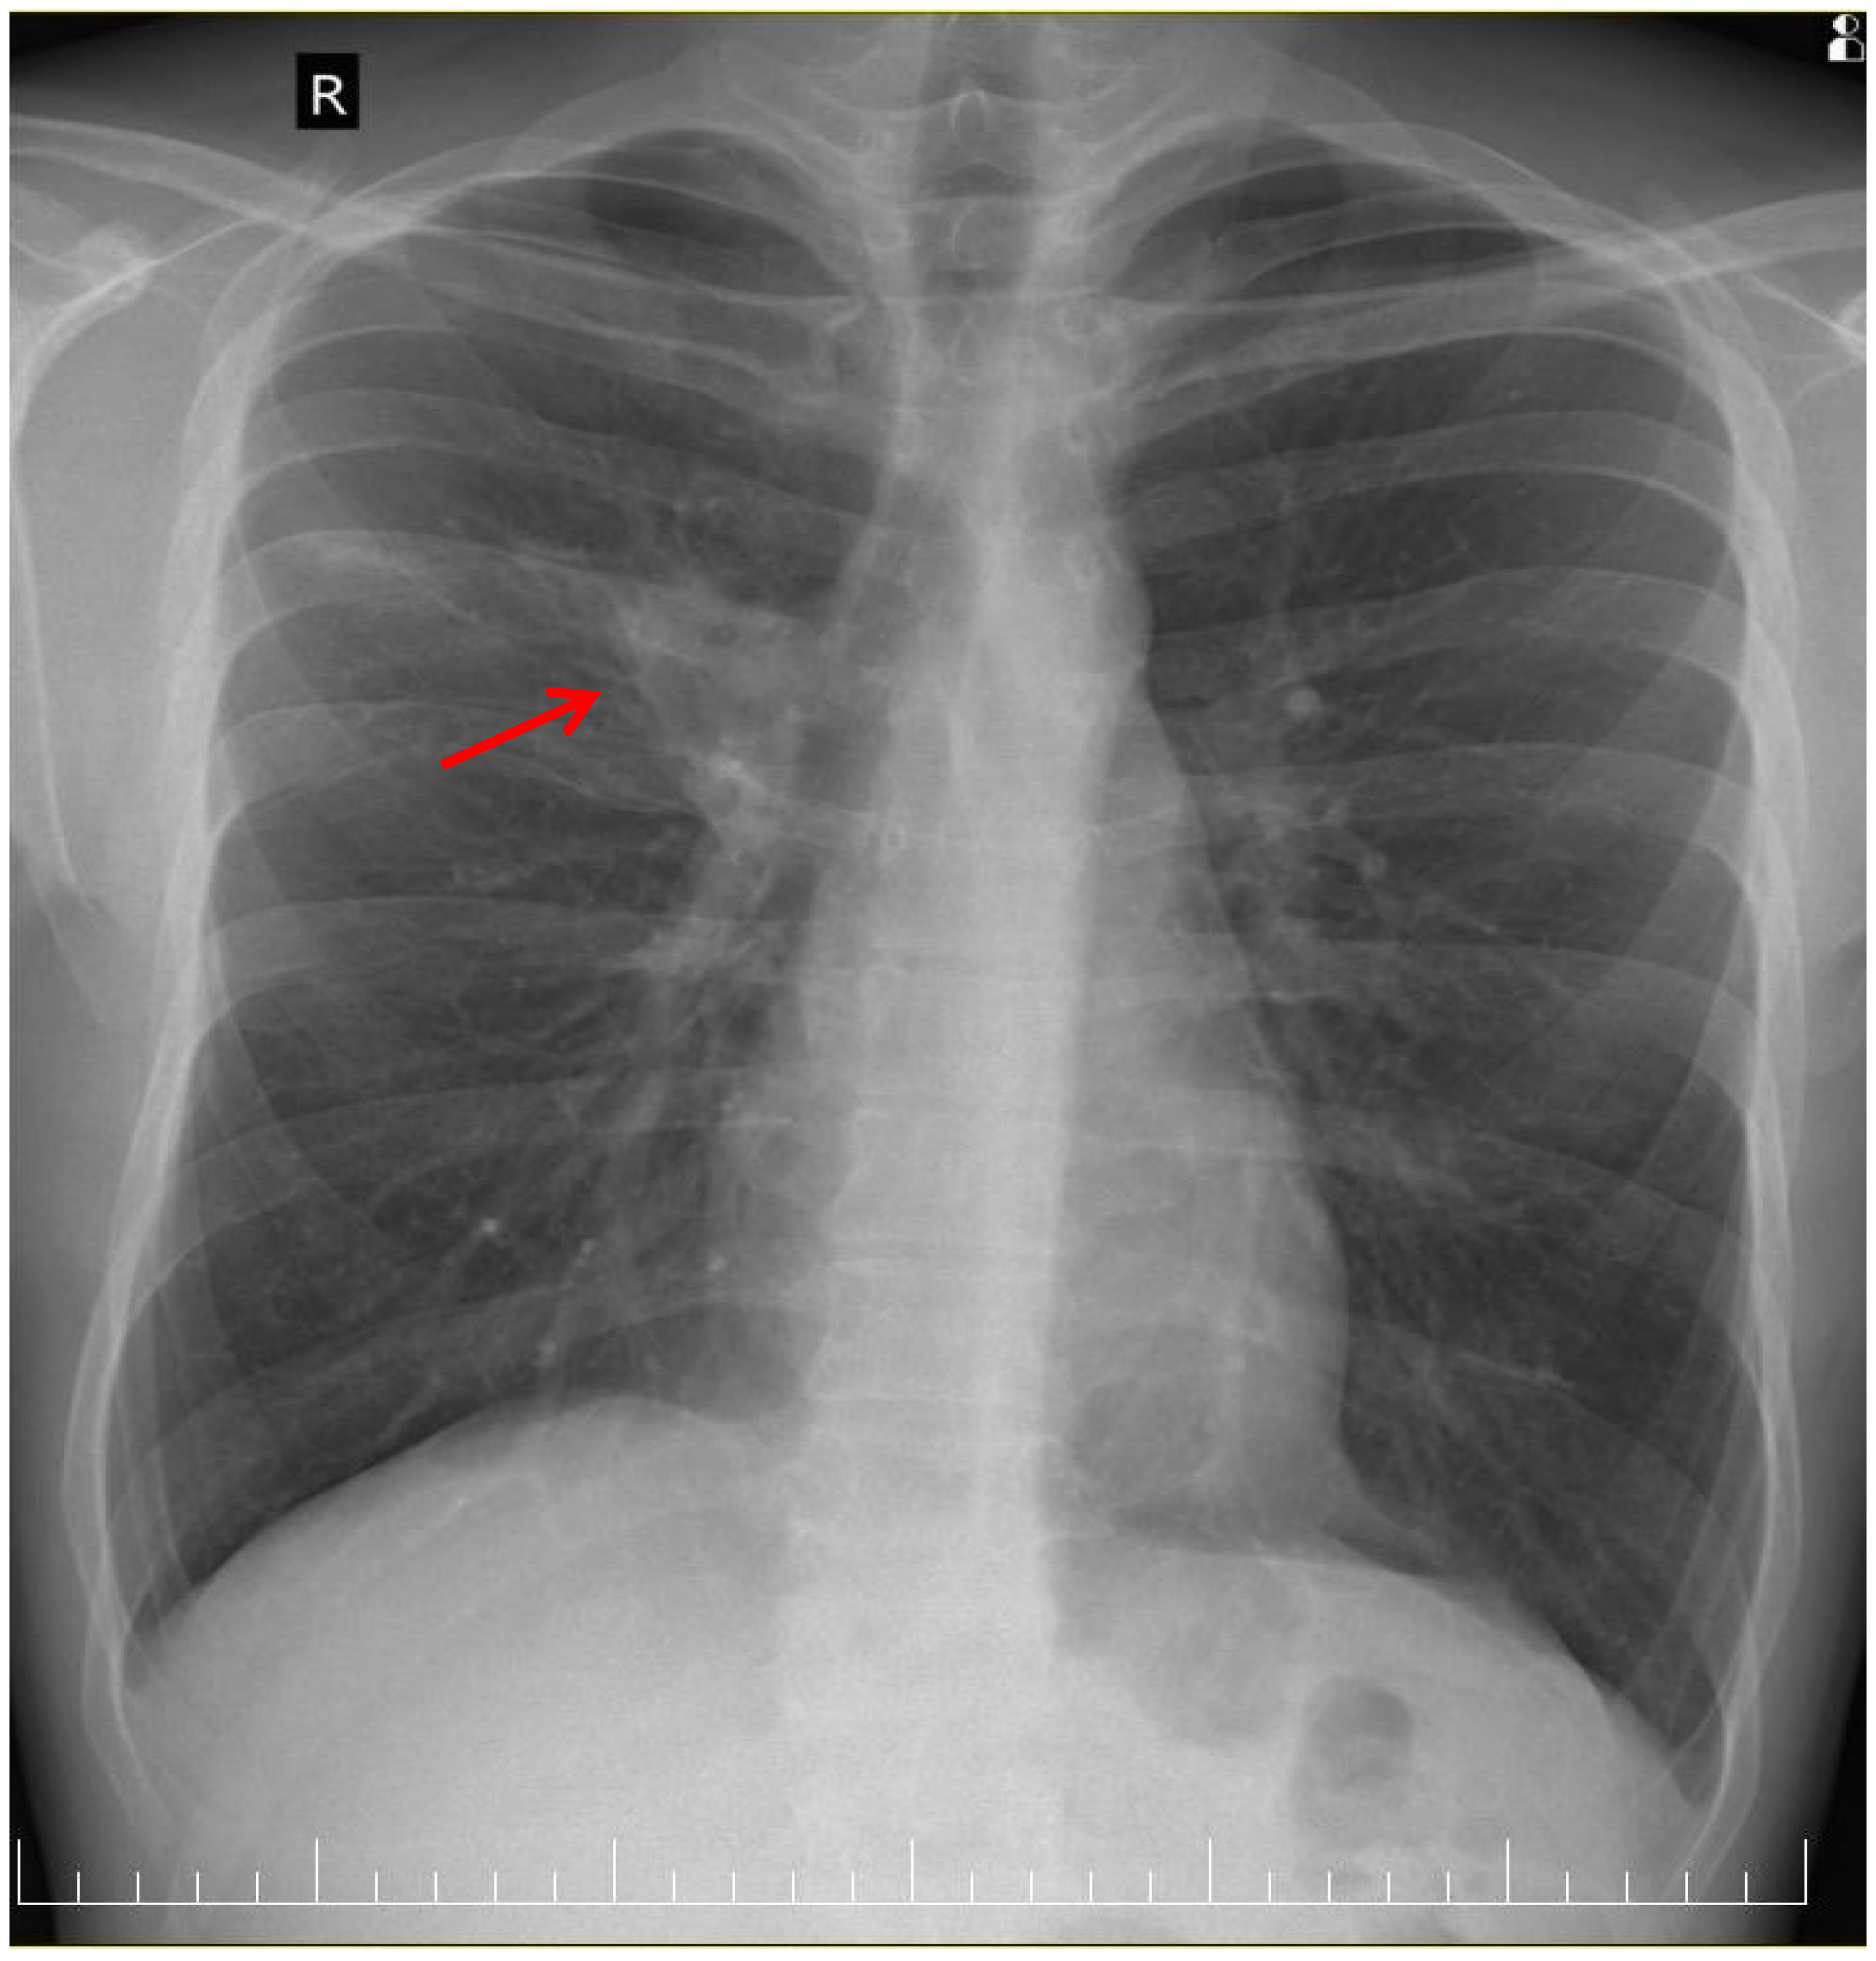

Serial chest radiographs over six months demonstrated a favorable radiological evolution, marked by the progressive resolution of pulmonary opacities, the absence of new infiltrative changes, and the lack of residual fibrotic or cavitary sequelae on follow-up imaging (Figure 4).

Figure 4. Chest X-ray at T6 shows complete resolution of right suprahilar opacity and no evidence of residual sequelae.